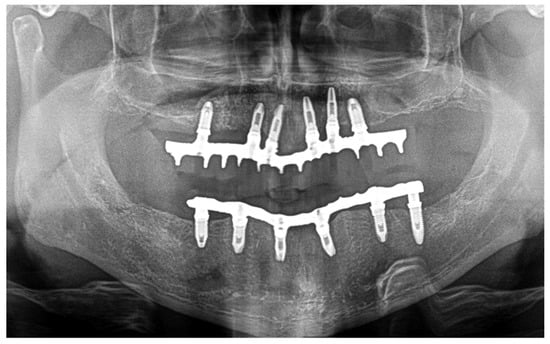

Immediate reconstruction of the defect was performed with an inferiorly based FAMM flap (Figure 3 and Figure 4) and immediate placement of 12 dental implants, 6 in the mandible and 6 in the maxilla (Figure 5). There were no postoperative complications, and the patient received postoperative radiotherapy (60 Gy). Eight months later, prosthetic rehabilitation of the dental implants was performed, and the aesthetic and functional evaluations were accomplished.

Mouth opening was evaluated as normal and lingual mobility as excellent for tip elevation, lingual protrusion, and lateral movements (Figure 6 and Figure 7). The patient was rehabilitated with two implant-supported prostheses (Figure 8, Figure 9 and Figure 10). Their speech articulation was evaluated as normal and the patient reported a normal diet without restrictions. From the aesthetic point of view, the patient reported an excellent result (Figure 11).

Figure 10. Panoramic radiograph after prosthetic rehabilitation with an implant-fixed prosthesis.

Jcm 10 03625 g010